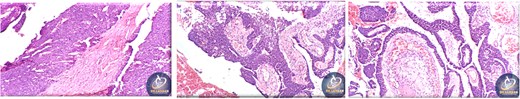

A 42-year-old male previously diagnosed with maxillary nasal sinus squamous cell carcinoma (SCC) was hospitalized for surgical treatment of recurrent infiltrating AC. The patient experienced three recurrences with the initial treatment approach for the cancer as SCC, a non-keratinizing variant. Complete excision and curettage of the lining mucosa were performed. In the second recurrence, the patient underwent additional curettage and subsequently revealed the absence of tumor residues from the mucosa and submucosa. However, the patient experienced a third recurrence with rapid growth and infiltration to the floor of the right maxillary sinus, filling the sinus space, infratemporal fossa, pterygopalatine fossa, cheek buccal area, and orbital floor. The imaging studies were preformed revealing a neoplastic lesion centered on the right maxillary sinus measuring 10 × 5 × 4.5 cm with a low T1 signal, heterogeneous iso T2/STIR signal, and intense heterogeneous post-contrast enhancement (Fig. 1). AC was recognized as stage II based on Yang’s et al. classification system [6]. Right Subtotal maxillectomy was performed through a Weber Ferguson incision with a Dieffenbach extension, and the infiltration areas were cleared. The excised tumor mass from the right maxillary sinus with labeled surgical margins (palate, orbital floor, buccal, and pterygoid surgical margins) was subjected to permanent paraffin evaluation (Fig. 2). The Right hemi-maxillectomy measuring 6 × 4.5 × 4 cm, revealed one canine, two molars, and two premolars found in the alveolar arch. An indefinite, grayish-white, infiltrating, fungating mass, approximately (⁓6 × 4 × 2.5 cm), was observed in the maxillary sinus. The cut surface of the mass was grayish-white and firm, with skeletal muscle attachment and noticeable infiltration into the underlying periosteum of the alveolar arch. Furthermore, labeled tumor tissue fragments measuring 4.7 × 2 × 2.5 cm and multiple smaller pieces collectively measuring 4 × 4 × 2 cm, showing similar characteristics, were stored in the same container. Microscopic examinations were performed at different magnifications. At a low magnification, the specimen revealed the presence of an infiltrative tumor with a biphasic pattern. The Islands and epithelial cell sheets are embedded in the fibrous stroma. The tumor islands exhibited a basaloid appearance with peripheral palisading, reverse polarity, and central stellate reticulum-like cells, reminiscent of ameloblastoma. However, these neoplastic epithelial cells exhibited moderate cytological atypia and increased mitotic activity, which suggests of malignancy (Fig. 3). Higher magnification shows tumor cells with enlarged, pleomorphic nuclei, prominent nucleoli, and eosinophilic cytoplasm. Frequent mitotic figures, including atypical forms, were also observed. Peripherally, tumor islands comprise cells with hyperchromatic elongated nuclei exhibiting focal palisading. The central cells were loosely cohesive and exhibited a stellate reticulum-like morphology. Additionally, focal areas of necrosis, hemorrhage, and keratinization were prominent in the tumor islands, and the surrounding stroma appeared desmoplastic and encompassed moderate chronic inflammatory infiltrates (Fig. 4). Additionally, diffuse infiltration of tumor into the adjacent tissues was observed, including bone and soft tissues, and is associated with perineural and lymphovascular invasion. Tumor extension in the orbital floor and buccal mucosal surgical margins was evident. In contrast, the palatal and pterygoid surgical margins are free of tumor involvement (Fig. 5). Overall, the morphological features were consistent with a diagnosis of infiltrating AC. Furthermore, immunohistochemistry assay was performed using a Ventana BenchMark GX Auto-stainer, employing the Ventana I View DAB detection system and Ventana monoclonal antibodies. The sections were stained for CK 5/6, P63, CK19, SOX-2, SOX-10, calretinin, and Ki67. The results revealed that the tumor basaloid epithelial component was strongly positive for P63 and showed weak heterogeneous positive staining for CK19, calretinin, and SOX-2 (Fig. 6). Conversely, it was negative for CK5/6 and SOX-10 staining. The Ki67 labeled index within the epithelial component was ⁓14%, whereas the mesenchymal component was 8%. The post-operative radiotherapy at 66 Gy was successfully administered. The patient is currently under observation, with careful follow-up.

Tumor extension to the orbital floor and buccal mucosal surgical margin.

Ancillary studies for CK 5/6, P63, CK19, SOX-2, SOX-10, calretinin, and Ki67.